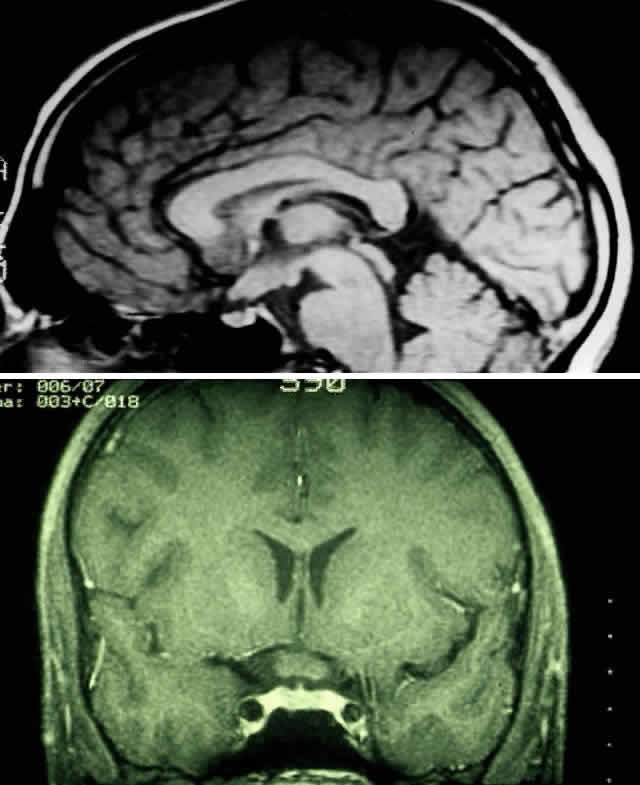

| Plain-film orbital X-ray may reveal concentric enlargement of the optic

foramen with preservation of a well-corticated margin due to a slow growth

of the tumor.4 A criterion for abnormality in one study that did not include any false-positives

in children is an optic foramen of 7 mm diameter, or 6.5 mm

and at least 1 mm larger than the contralateral foramen.67 Enlargement of the optic canal does not necessarily imply intracranial

extension of the glioma, because dural thickening and arachnoid hyperplasia

may cause such changes.68,69 In the series of Chutorian and colleagues, foramen enlargement was present

in 83% of patients with involvement of one optic nerve and in 67% of

those with chiasmal involvement.29 The pressure of the glioma on the anterior clinoid process and lateral

chiasmatic groove may produce a fossa with continuity of the optic canal, creating

a J-, pear-, or gourd-shaped sella turcica.70 Tumors that less commonly produce a similar flattening include trans-canalicular

extension of intraorbital neurofibromas, perioptic extension

of a craniopharyngioma, or pituitary adenoma.4 With the availability of computerized tomography (CT) and magnetic resonance imaging (MRI), invasive diagnostic techniques such as arteriography and pneumoencephalography should not be performed in the routine workup of presumed optic gliomas.71 CT scanning may demonstrate enlargement of the optic nerve or chiasm by a glioma (Fig. 3). Because optic gliomas typically appear isodense to normal brain,72 and because the degree of contrast enhancement ranges from imperceptible to moderate on CT imaging,73 the margins of the tumor may not be well delineated. Optic gliomas usually have a well-outlined fusiform shape, which may include kinking or buckling of the optic nerve. Chiasmal tumor appearance may range from a tubular thickening of both optic nerves and chiasm to massive, multilobular growths.74 Cystic spaces representing mucinous accumulation have been described. These cysts may enlarge and damage adjacent structures, requiring surgical intervention.74,75 Calcific change has also been documented in gliomas, but it is a rare radiologic finding.13 In following patients clinically, it is important to understand that radiologic progression of optic gliomas on CT scans may not correlate clinically with worsening visual function. Conversely, a decline or improvement in visual status may occur despite a lack of corresponding changes on neuroimaging.73,76 MRI has replaced CT scanning as the optimum test for imaging optic gliomas (Fig. 4 A and B). Optic gliomas have normal to slightly prolonged T1 relaxation times and appear isointense to slightly hypointense to normal brain on T1. Because many of these tumors have prolonged T2 relaxation times, images that are T2 weighted may be used to assess gross tumor margins and posterior extension.72 Optic nerve gliomas often demonstrate minimal enhancement after administration of contrast. To improve MR imaging of optic nerve lesions, a gadopentetate dimeglumine enhancement technique combined with fat suppression can be utilized. Unlike meningiomas, the thickened sheath from arachnoid hyperplasia associated with gliomas will not enhance.77 Although imaging should initially be performed in the axial plane to allow visualization of both the optic nerve and the posterior optic pathways, sagittal views are helpful in demonstrating chiasmal involvement; coronal views can be utilized to delineate intracanalicular tumor.78 MRI has several advantages over CT scanning. In addition to sparing children from exposure to ionizing radiation when multiple scans are required, MRI eliminates bony artifact and is superior in evaluating the intracanalicular, chiasmal, and postchiasmal extension of the tumor.78 Brown and associates79 reported 10 posteriorly located lesions by MRI, none of which were visualized by CT. Anterior pathway lesions were detected with equal sensitivity by both modalities. Unfortunately, microscopic spread of gliomas can go undetected by both CT and MRI. In addition to detecting bilateral optic nerve glioma, other MRI findings can suggest an association between an optic nerve glioma and NF-1. One imaging characteristic to watch for is double-intensity tubular thickening, which is seen as a high T2 signal surrounding the optic nerve. This radiologic finding has been termed a “pseudo-CSF” signal and can be misinterpreted as cerebrospinal fluid in a dilated subarachnoid space.80 The high T2 signal arises from perineural arachnoidal gliomatosis, a histopathologic pattern most commonly seen in NF-1-associated gliomas.60 Elongation of the nerve secondary to axial growth of the perineural tumor as well as downward kinking of the nerve in the midorbit are other features suggestive of NF-1-related gliomas.80 Neuroimaging studies have demonstrated that NF-1 patients may have more extensive glioma involvement of the visual pathway than patients who do not have NF-1.79,81 Despite this difference in visual pathway involvement, the same investigators81 noted a lower incidence of progressive neurologic deficits and visual symptoms in NF-1-related glioma patients compared with patients whose gliomas were unrelated to NF-1. MRI scanning of NF-1 patients may also demonstrate aqueductal stenosis, idiopathic macrocephaly, and unidentified T2-weighted signals in the basal ganglia, internal capsule, midbrain, cerebellum, and subcortical white matter.51,64,82 In the appropriate clinical setting, characteristic neuroimaging appearances consistent with intrinsic optic pathway enlargement can usually permit a diagnosis without a surgical biopsy.13,71 Hoyt and associates73,74 noted the following radiologic features on CT scanning that they considered diagnostic for optic chiasm gliomas:

Globular tumors in the suprasellar area that lack these features usually require craniotomy and biopsy confirmation. Lesions that may be difficult to distinguish from optic pathway gliomas include germinomas of the visual system and optic nerve choristoma because they both may appear intrinsic to the visual pathway.13 Tumors such as craniopharyngiomas and pituitary adenomas usually do not appear intrinsic to the visual pathway and may have features of sellar enlargement. Findings such as enhancement of the leptomeninges or peripheral enhancement of an enlarged chiasm are atypical of optic glioma and may indicate an inflammatory process masquerading as a glioma.83 Aneurysms in the suprasellar area may sometimes appear on neuroimaging to be intrinsic to the visual pathway. Better definition may be noted with magnetic resonance angiography.13 In contrast to orbital optic nerve gliomas, meningiomas enhance strongly with gadolinium and are less common in children. Meningiomas have the following features on axial CT scanning that are not typically shared by optic nerve gliomas: